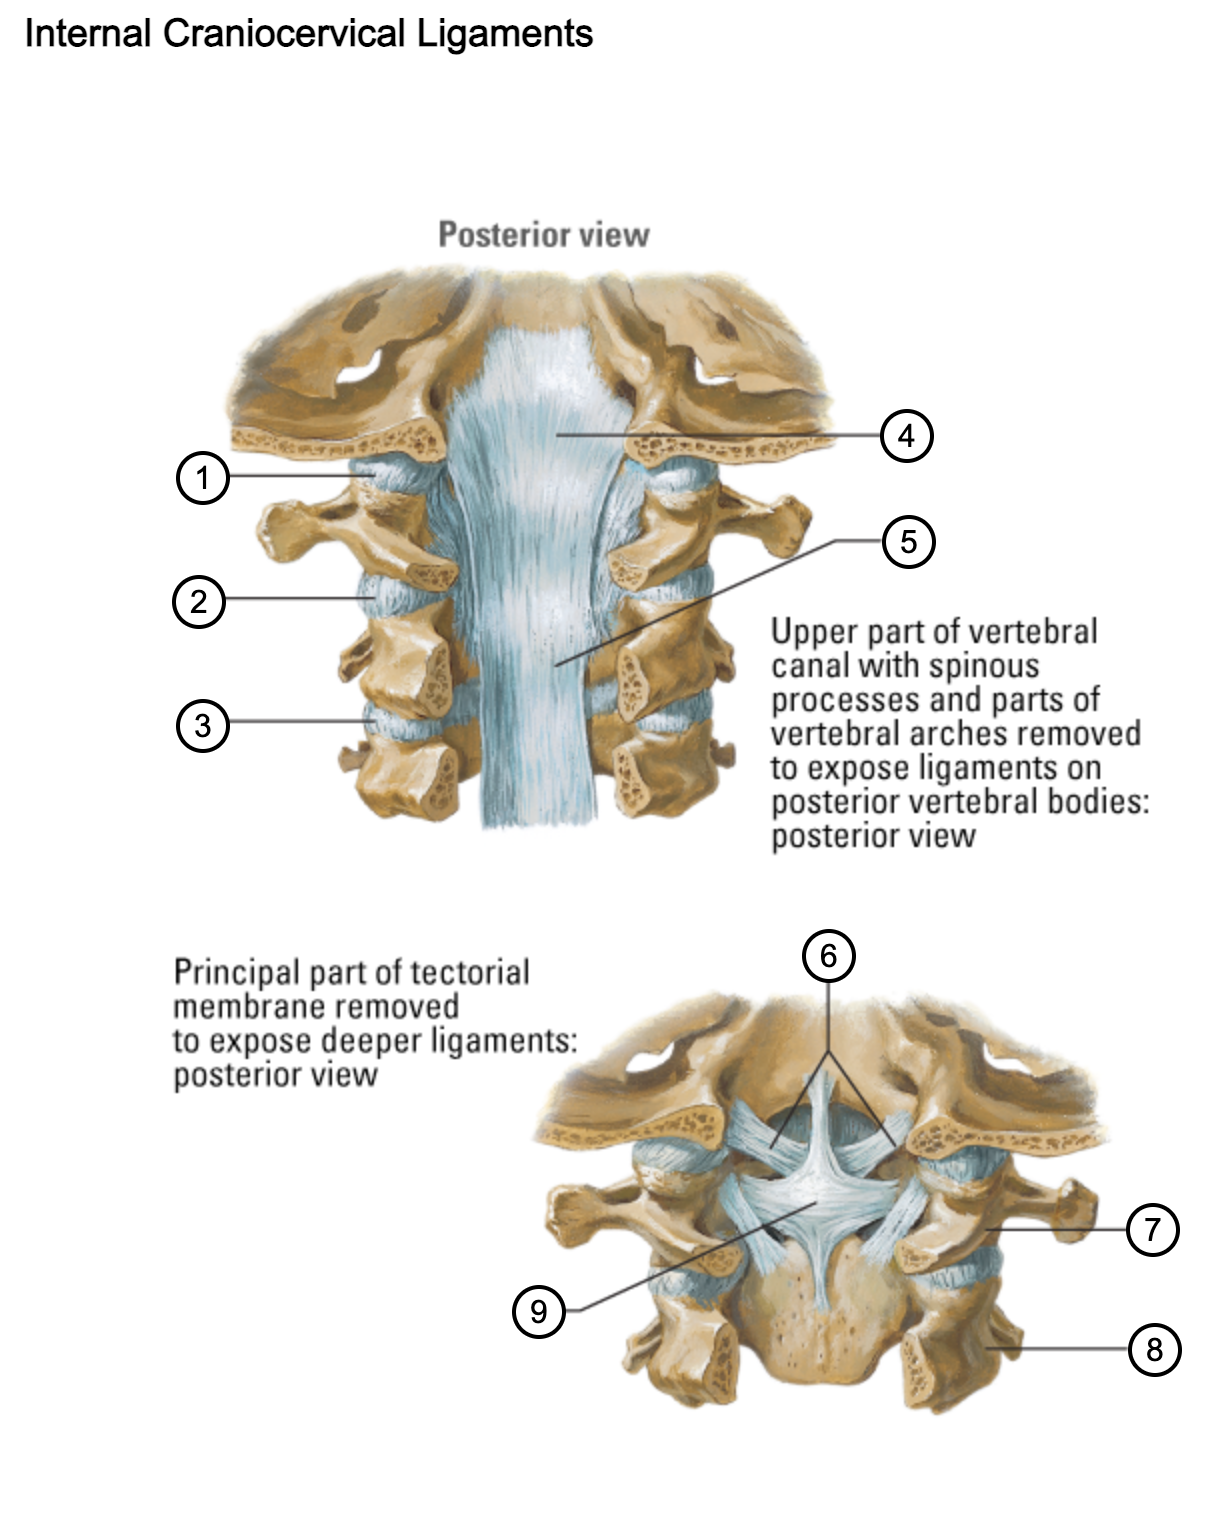

1

capsule of atlantooccipital joint

2

capsule of lateral atlantoaxial joint

3

capsule of zygapophysial joint (between axis and C3 vertebra)

4

tectorial membrane of cervical vertebral column

5

posterior longitudinal ligament

6

alar ligaments

7

atlas (C1)

8

axis (C2)

9

cruciform ligament (superior longitudinal band; transverse ligament of atlas; inferior longitudinal band)